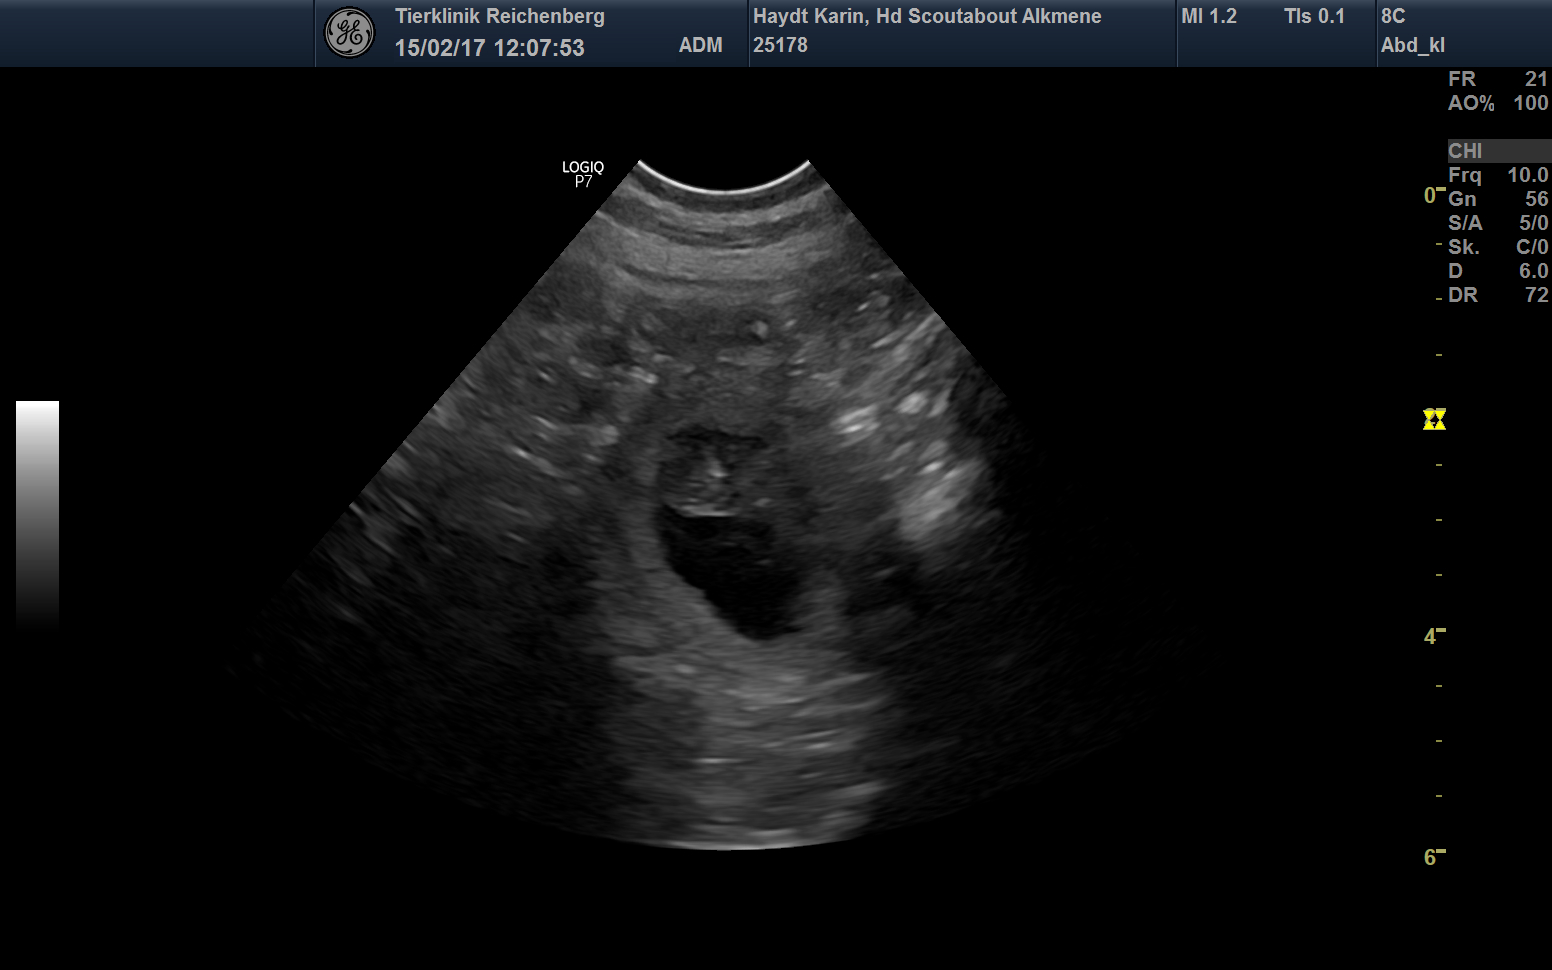

Wir erwarten Welpen !

Ein erster Blick auf die Babys